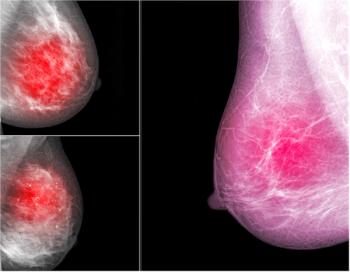

Not all women with dense breast tissue have a high risk of breast cancer, but they all have an increased risk compared with women who have average tissue density. Can this patient population benefit from screening with abbreviated breast magnetic resonance imaging (AB MRI) over digital breast tomosynthesis?